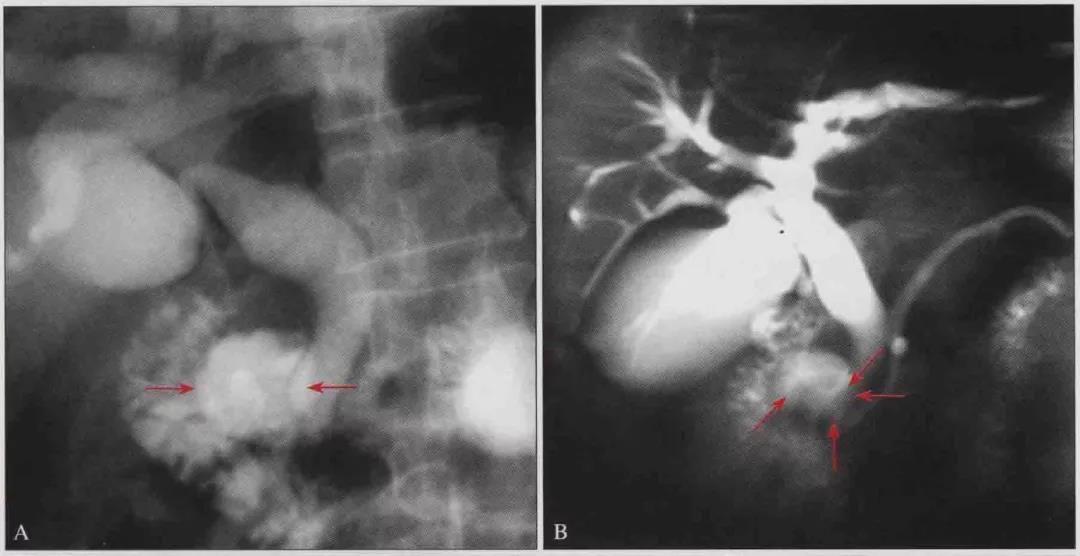

上消化道钡餐透视:十二指肠降段乳头旁憩室,与肝胰壶腹关系密切(图-1A,B)

图-1 Lemmel综合征